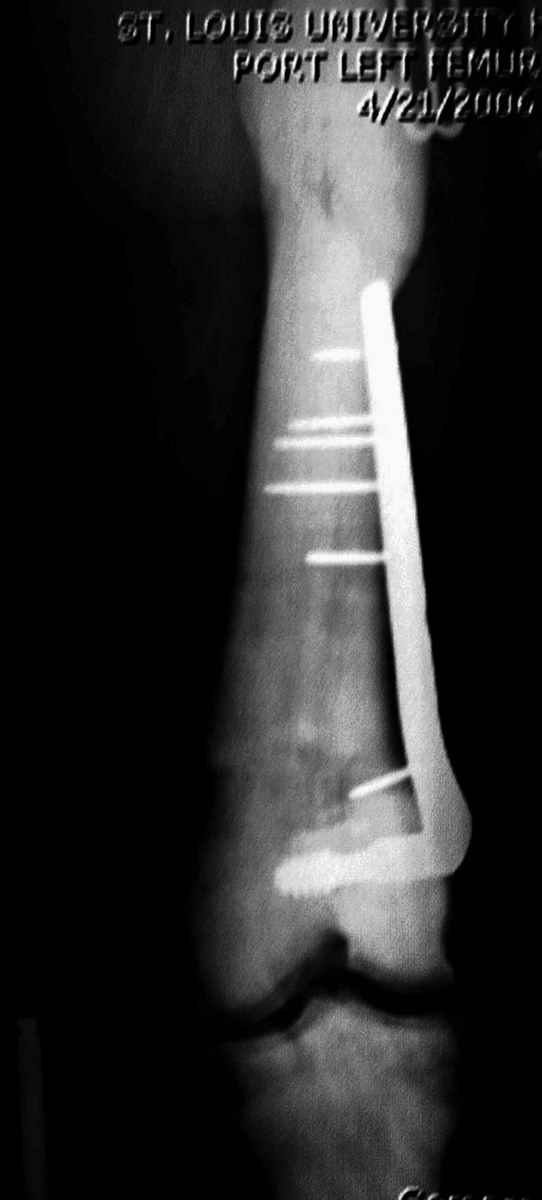

Re: [2/3] Перелом проксимального бедра

Здесь у меня дополнительные снимки с большим разрешением и в разных режимах, а то те дигитал снимки совсем очень блеклые, может, эти изображени изменят выбор тактики